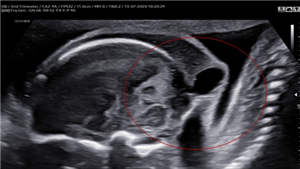

CLS: Báo cáo một trường hợp khiếm khuyết ống thần kinh hiếm gặp: Iniencephaly

Xem thêm